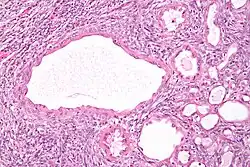

| Micrograph of a cystic nephroma (left of image). Normal kidney is seen on the right. H&E stain. | |

High magnification micrograph of a cystic nephroma showing the characteristic simple epithelium with hobnail morphology, and the ovarian-like stroma. H&E stain.

The characteristics of cystic nephromas are:

- Cysts lined by a simple epithelium with a hobnail morphology, i.e. the nuclei of the cyst lining epithelium bulges into the lumen of the cysts,

- Ovarian-like stroma that has a:

- Spindle cell morphology, and has a

- Basophilic cytoplasm.

Micrograph of a cystic nephroma. H&E stain.